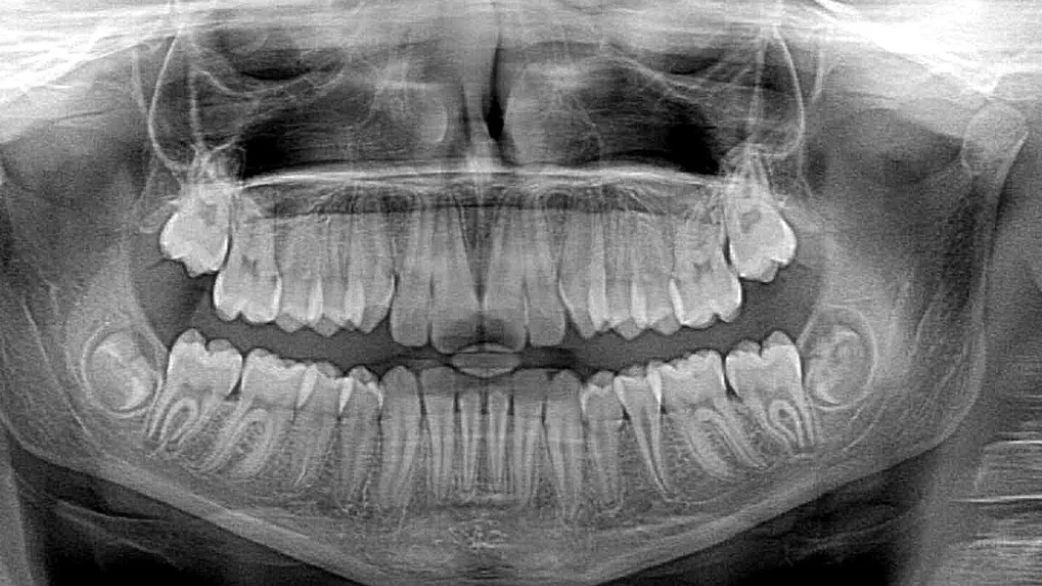

• rentgen zęba (rentgen pantomograficzny, cefalometryczny lub punktowy) to badanie wykonywane podczas leczenia kanałowego czy ortodontycznego, przed ekstrakcją zęba, przy diagnozowaniu próchnicy oraz stanów zapalnych zębów,